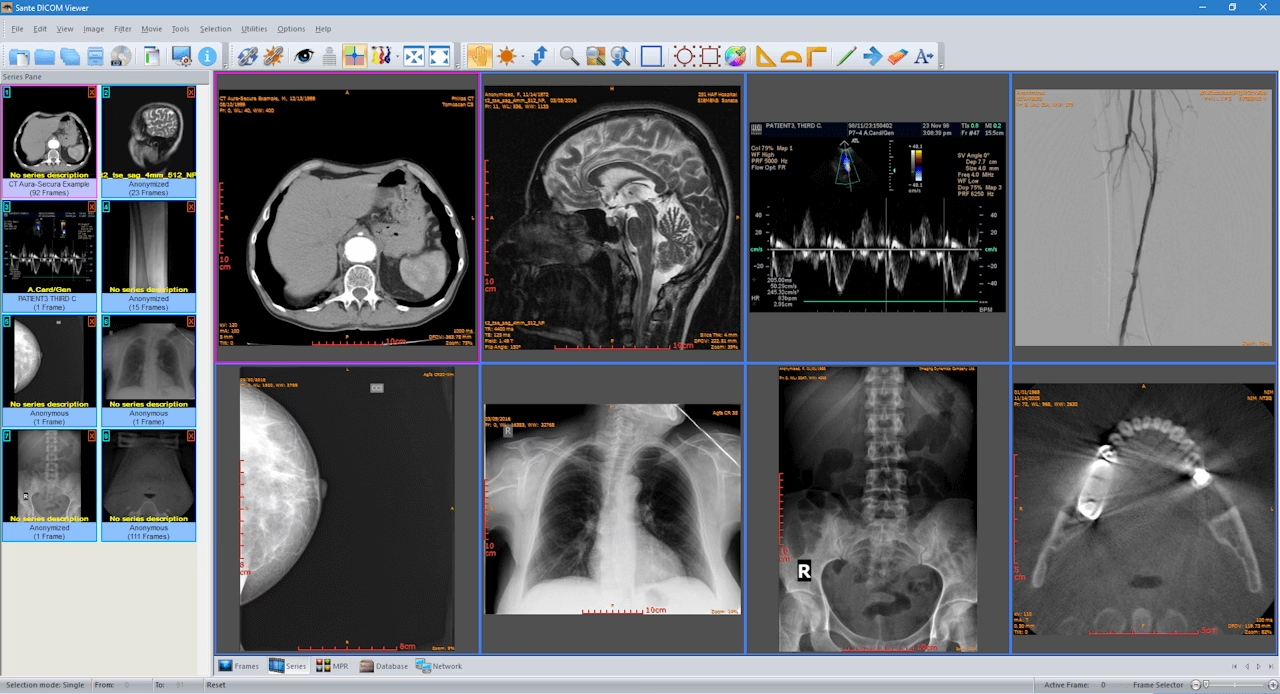

Deși Mango este un instrument extrem de puternic și versatil, există și alte vizualizatoare DICOM populare pe piață, fiecare cu propriile sale puncte forte și public țintă. Înțelegerea diferențelor dintre aceste instrumente este crucială pentru a alege soluția potrivită nevoilor specifice. Iată o comparație sumară cu câteva dintre cele mai cunoscute alternative, bazată pe informațiile disponibile:

| Software | Platforme Suportate | Cost | Puncte Forte Principale | Public Țintă Principal |

|---|---|---|---|---|

| Mango | Desktop (Mac OS X, Windows, Linux), Browser (Papaya), Mobil (Apple iPad) | Nespecificat (tipic pentru cercetare, adesea gratuit/open-source sau licențiat) | Analiză multi-imagine avansată, editare ROI sofisticată, randare suprafețe 3D, înregistrare imagini, personalizare extinsă, suport nativ pentru DICOM, NIFTI, Analyze. | Cercetători, neurologi, radiologi, studenți în medicină, profesioniști în imagistică medicală. |

| Horos | macOS | Gratuit, Open Source | Vizualizator DICOM 64-bit, reconstrucție 2D/3D multi-planar, randare suprafețe și volum, Maximum Intensity Projection (MIP), instrumente de anonimizare, suport pentru plugin-uri și scripting. | Comunitatea medicală (cercetare, educație, non-diagnostic), utilizatori macOS. |

| Pro Surgical 3D | Nespecificat (compatibil cu diverse modalități, probabil Windows/macOS) | Gratuit, FDA-cleared | Vizualizări 3D de înaltă calitate, randare avansată suprafețe și volum, reformatare multi-planar. Conceput pentru planificare chirurgicală preoperativă precisă și analiză clinică îmbunătățită. | Chirurgi, specialiști în planificare preoperativă, profesioniști care necesită modele anatomice precise. |

| RadiAnt DICOM Viewer | Windows (executabil standalone) | Comercial (cu versiune de încercare disponibilă) | Performanță rapidă și fiabilă, interfață intuitivă, suport multi-touch, redare multi-frame și cine loop, comparație studii, modul puternic de reconstrucție 3D, export imagini. Portabil. | Medici, radiologi, clinicieni, studenți, pentru vizualizare rapidă și analiză esențială. |

Fiecare dintre aceste instrumente are o nișă specifică. Mango excelează în cercetarea multi-imagine și analiza aprofundată, oferind o flexibilitate considerabilă prin personalizare. Horos este o opțiune robustă și gratuită pentru utilizatorii macOS, ideală pentru explorare și dezvoltare. Pro Surgical 3D se concentrează pe planificarea chirurgicală cu vizualizări 3D de înaltă fidelitate, iar RadiAnt oferă o soluție rapidă, portabilă și eficientă pentru vizualizarea clinică de zi cu zi.